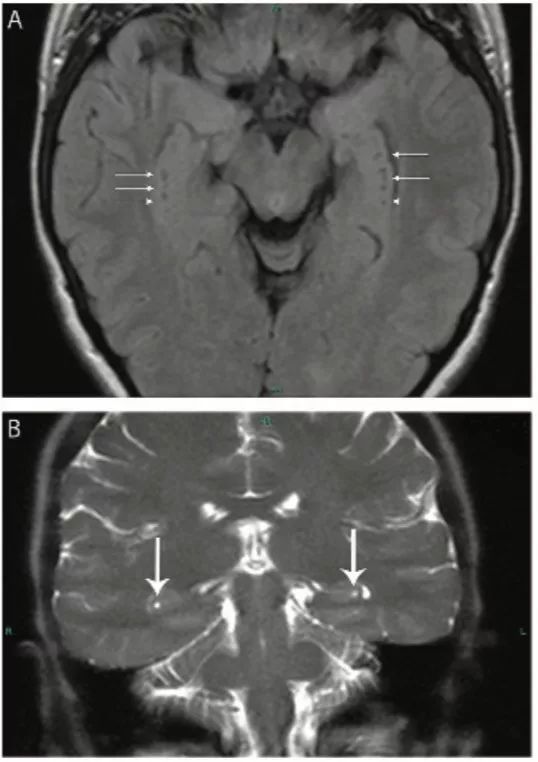

图3 脉络膜裂神经上皮囊肿

(A) 冠状位T2WI显示位于海马区上方,起源于脉络膜裂的囊肿(箭头);(B)FLAIR像显示同一囊肿(箭头)位于中脑外侧、颞叶内侧。

图6 海马沟残余囊肿

轴位FLAIR像(A)和冠状位T2WI像(B)显示双侧侧脑室内侧、颞叶小腔隙灶 (箭头)。